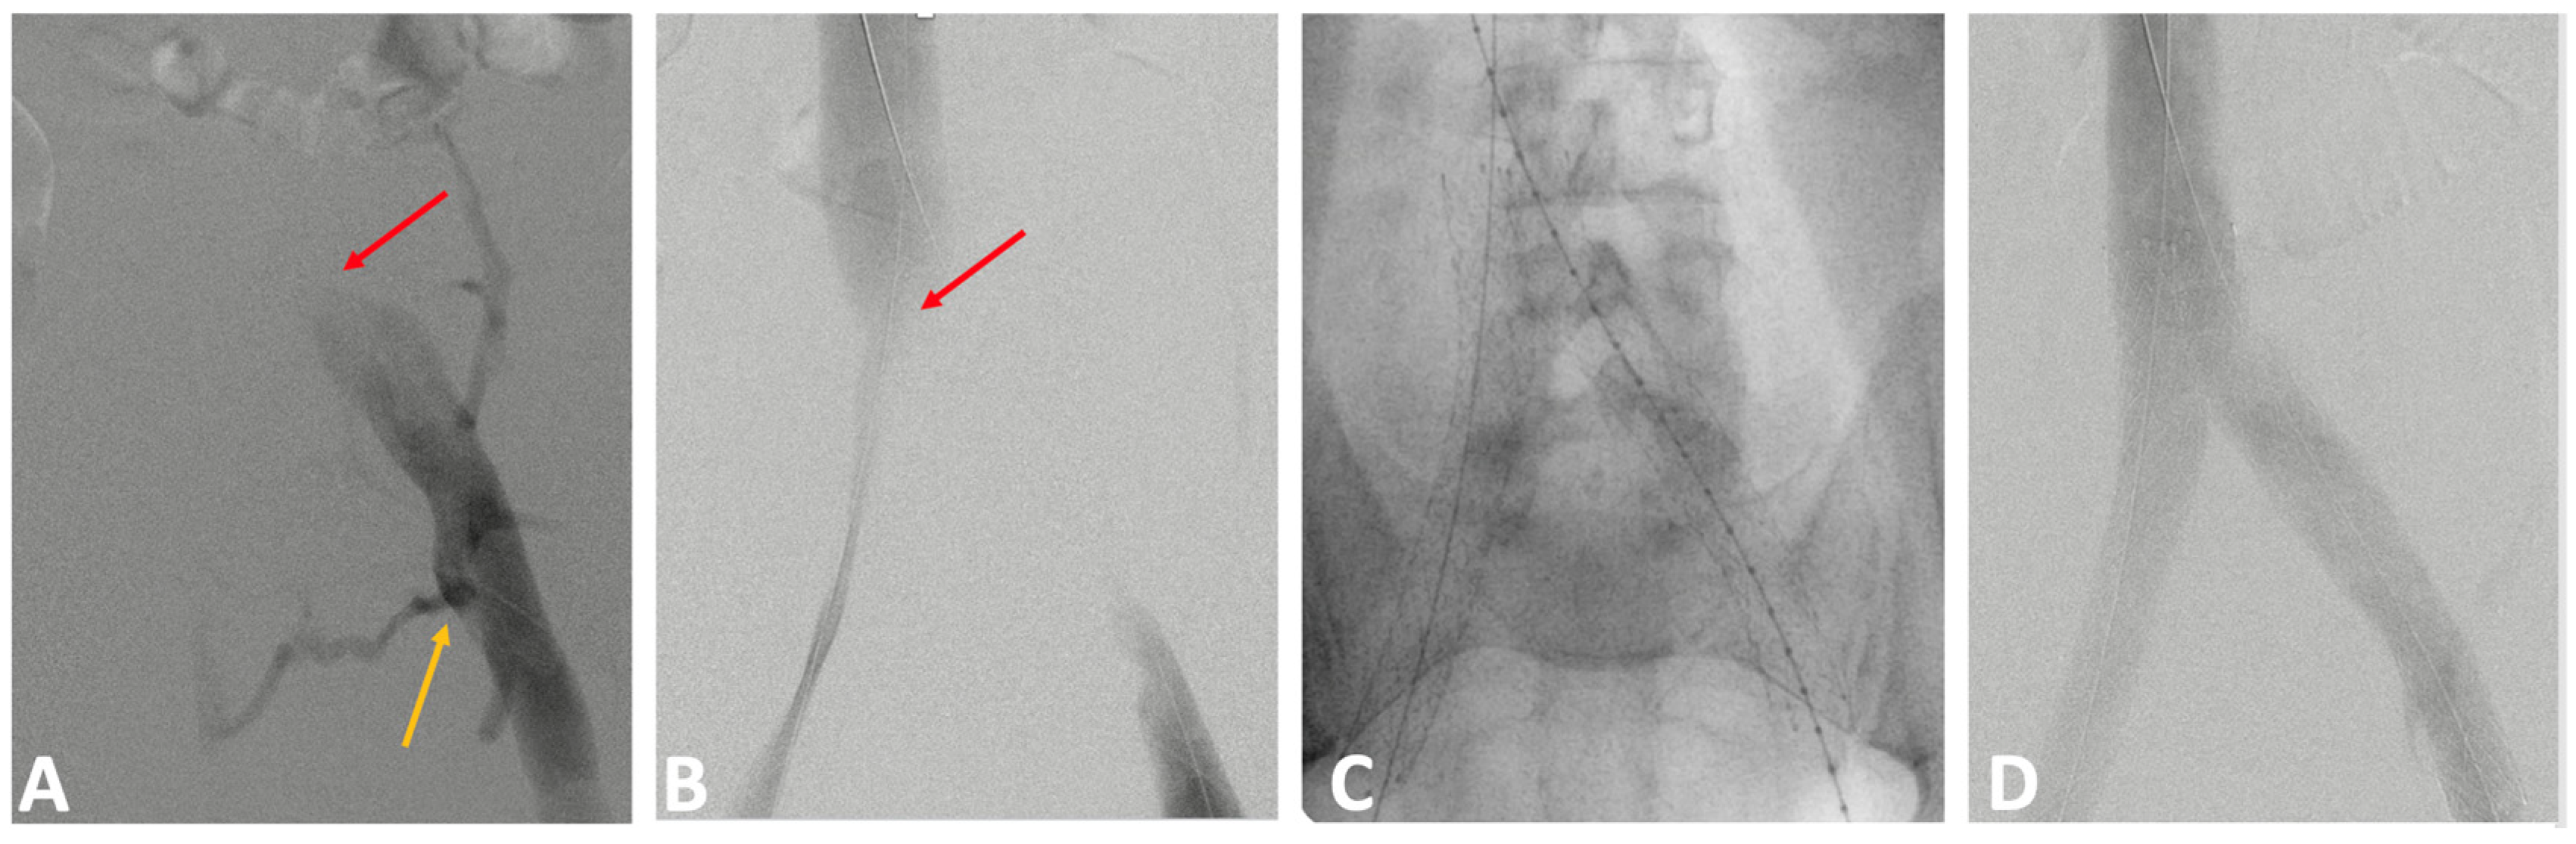

2.3.2. Catheter Venography and Intravascular Ultrasound